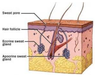

the dermis contains what?

6 listed

Identify

What is this and where is it found?

Sebaceous Gland Description

4 listed

Where are Sebaceous Glands not found

What is the Hypodermis?

Hypodermis AKA